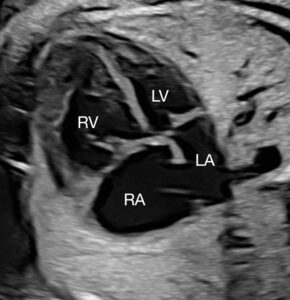

Prenatal diagnosis of coarctation of the aorta through fetal echocardiography is tricky, with the ductus arteriosus often interfering with identification of the coarctation. Taking measurements and drawing conclusions about associated left-heart hypoplasia is complicated by numerous factors. A small mitral valve accompanied by a small left ventricle that is long and narrow may ultimately place the infant in the normal range after birth, while short, wide left ventricles are often inadequate for a biventricular course postnatally.

The team conducted a retrospective review from 2010 to 2020 of 67 fetuses with postnatally confirmed coarctation of the aorta, excluding those with other major congenital heart defects. They used fetal ultrasound to measure the mitral valves and compared the results between groups with postnatal biventricular repair versus single-ventricle palliation, death or transplantation outcomes.

The researchers also looked at measurements of the left ventricle, aortic arch and aortic valve and the direction of flow across the foramen ovale. Of all of these, however, the size of the mitral valve was found to have the highest correlation with the postnatal surgical course, though at a different threshold than historically presumed.